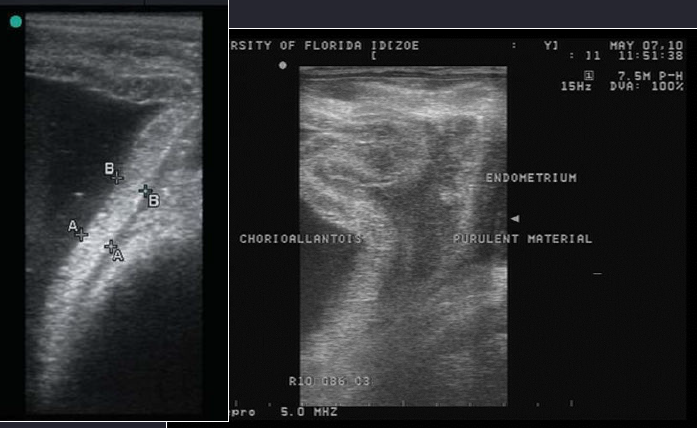

Quels sont les deux signes qui nous permettent de détecter la placentite chez la jument ?

• Épaississement du placenta (ECUP) et séparation placentaire (séparation de l’endomètre)

ECUP : Mesure combinée de l’épaisseur du placenta et de l’utérus

Séparation placentaire = « Red bag » au niveau de l’étoile cervicale